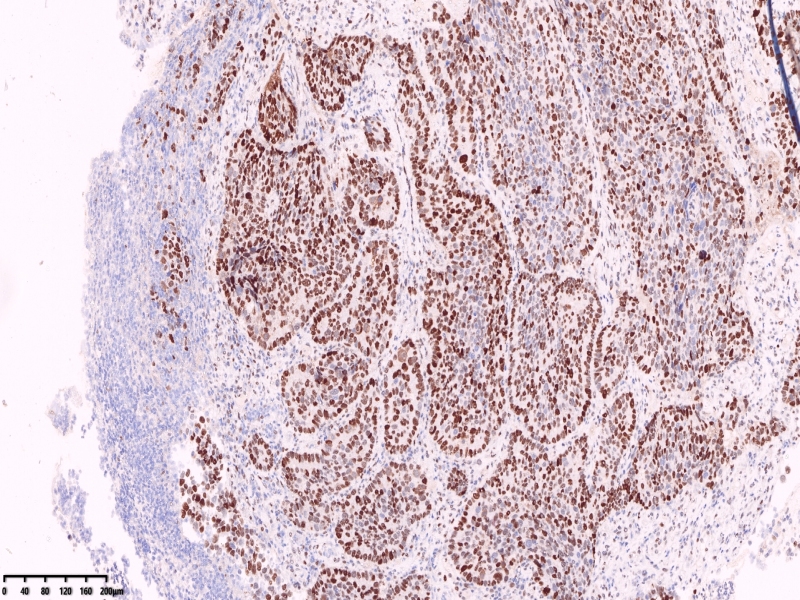

CK7